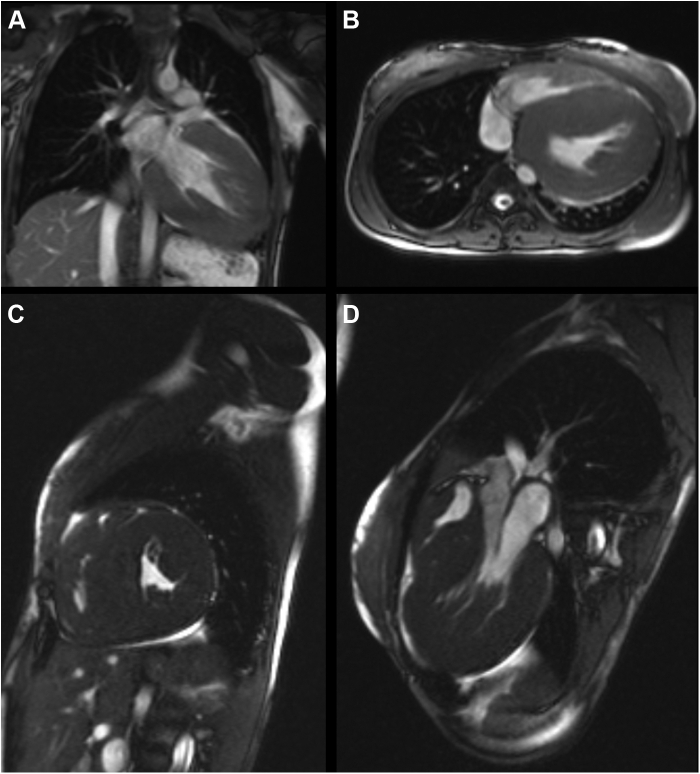

Figure 4.

Cardiovascular magnetic resonance showing severe free-wall and septal left ventricular hypertrophy in (A) coronal, (B) axial, (C) sagittal, and (D) oblique long-axis displays.